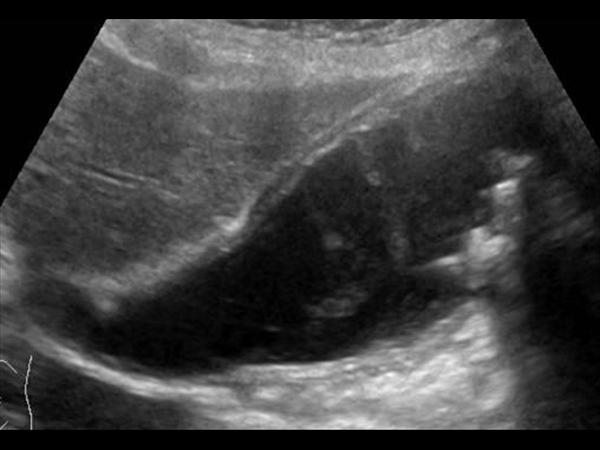

Viêm túi mật

» Thông tin: Nữ giới – 87 tuổi.

» Lâm sàng: Đau mạn sườn phải / Sốt.